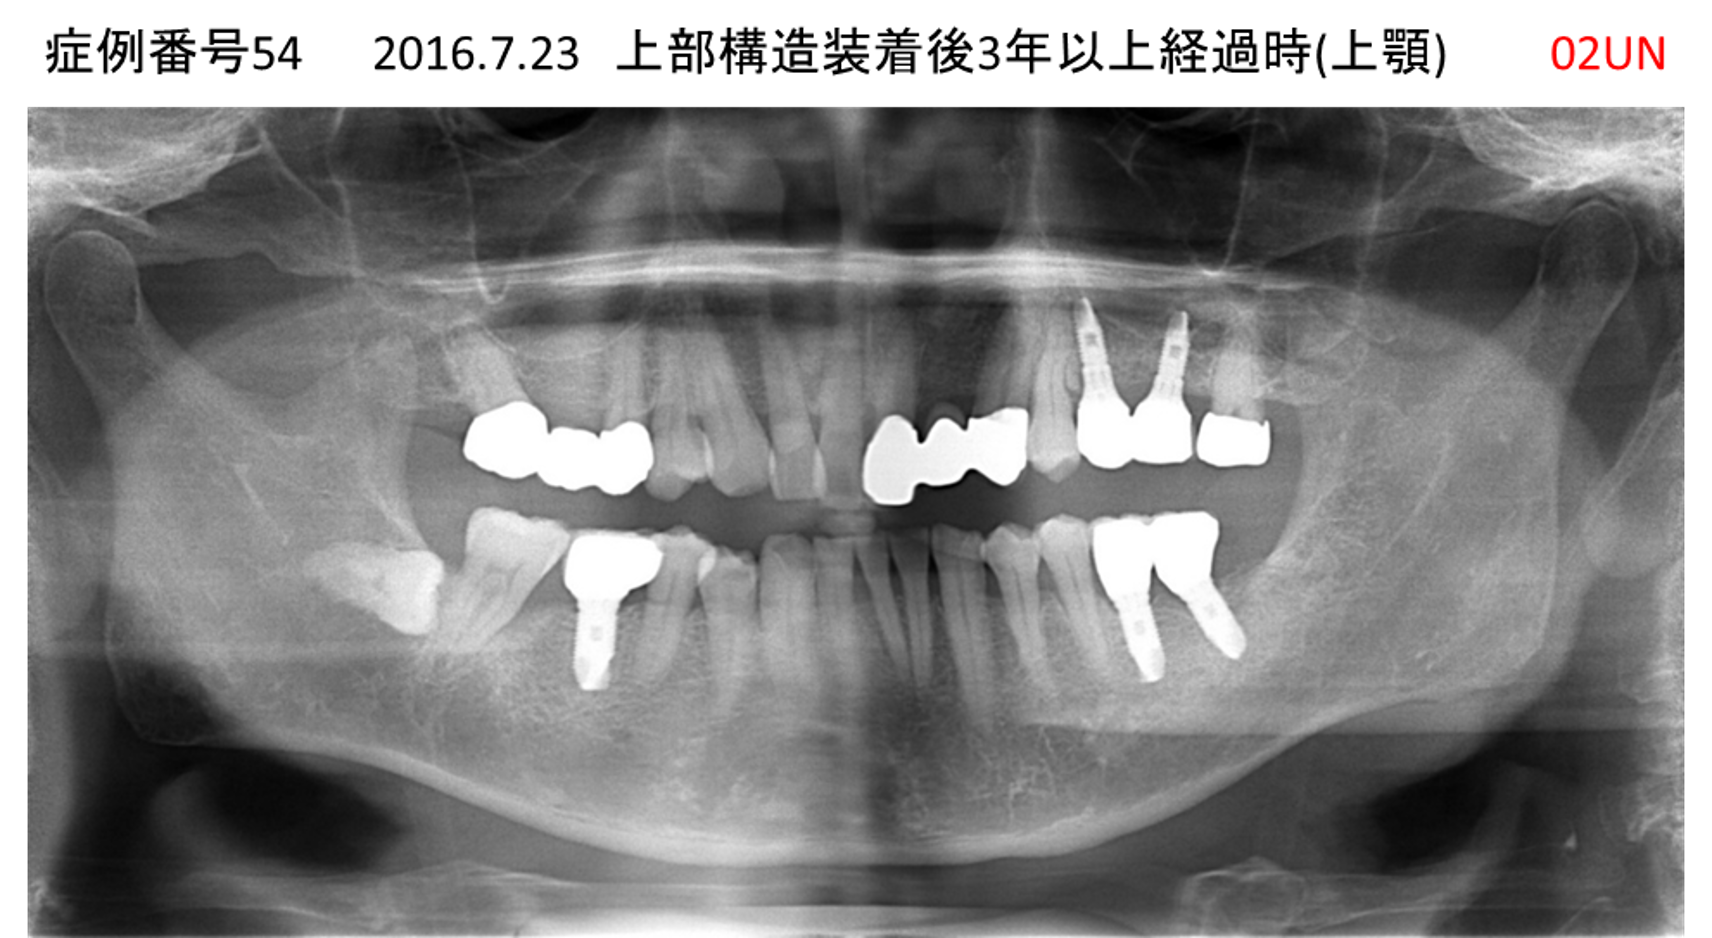

ご飯を美味しく食べたい/人前で笑えるようになりたい患者様のインプラント症例

| 治療名称 |

インプラント |

| 治療費用 |

480万円+税 |

| 治療期間 |

6か月 |

| 患者さんの症状(主訴) |

おいしいご飯が食べられるようになりたい 人前で笑えるようになりたい |

| 治療内容 |

サイナスリフト 抜歯即時インプラント |

| 治療結果 |

何でも食べられるようになった 人前で大口を開けて笑えるようになった |

| 治療の注意点(リスク/副作用) |

インプラントが壊れた場合は再治療が必要 |